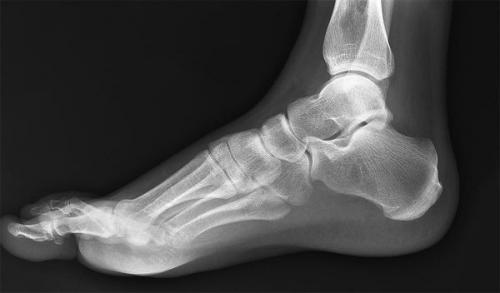

Утолщение суставов на запястье и голеностоп. Информативность метода

Диагностика патологических процессов методом рентгенографии заключается в получении и анализе двухмерного изображения тканей на снимке (рентгенограмме), получаемого при воздействии на орган рентгеновскими лучами. Наиболее отчетливо на снимке визуализированы объекты, имеющее более плотную структуру. Рентген голеностопного сустава позволяет с высокой степенью точности оценить состояние костных тканей, из которых он состоит. К ним относятся:

- Большеберцовая кость голени. В нижнем эпифизе она переходит в медиальную лодыжку, суставная поверхность которой охватывает таранную кость.

- Малоберцовая, сочлененная внизу с таранной костью. Дистальный конец кости является наружной лодыжкой блока голеностопного сустава.

- Таранная кость (надпяточная), являющаяся нижней частью голеностопного сустава. Она распределяет вес человека на всю стопу и покрыта суставным хрящом.

Также голеностопный сустав включает наружную и внутреннюю группу связок, связки межберцового синдесмоза; пучки сухожилий (наиболее значимое в организме человека ахиллово сухожилие); группы мышц, называемые сгибателями и разгибателями стопы; сосуды; нервные окончания. Они видны на рентгенограмме менее отчетливо.

Повреждение сустава нарушает подвижность стопы, лишает возможности сохранять положение тела на неровной поверхности, снижает ее амортизирующие функции, а значит ухудшает качество жизни. Поэтому необходима быстрая и верная диагностика для выявления и устранения причин болезненного состояния.